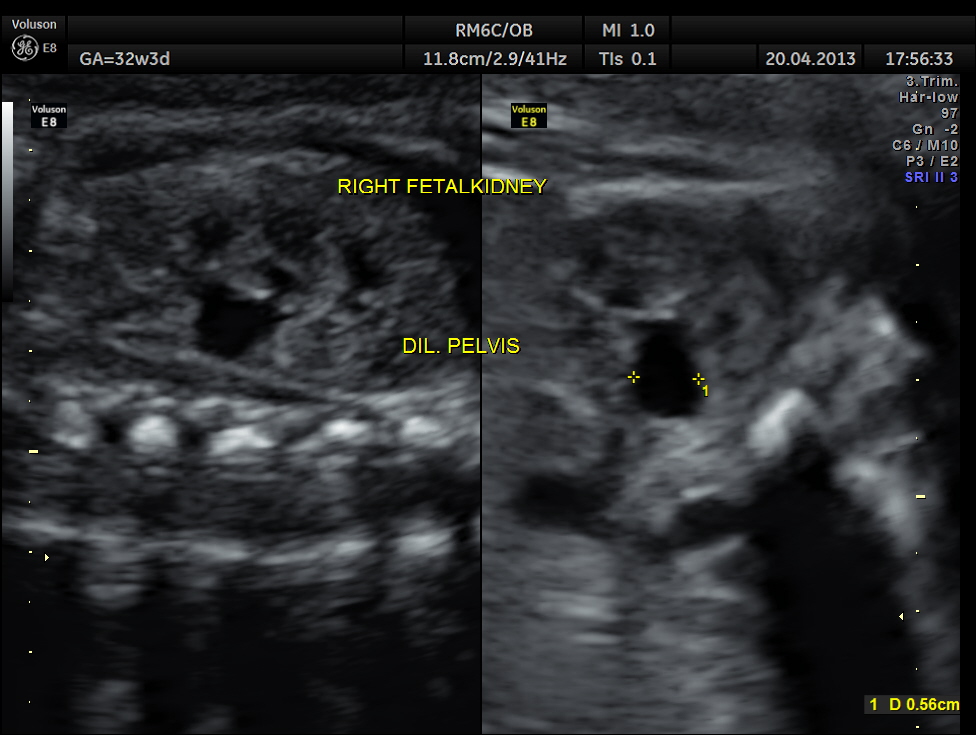

The following images show bilateral renal pelvi ectasis and bilateral dilated ureters with all the changes more in the left kidney .

The left kidney also showed possible duple-ix pelvis with double ureters arising from them . But this finding could not be confirmed in all the views .